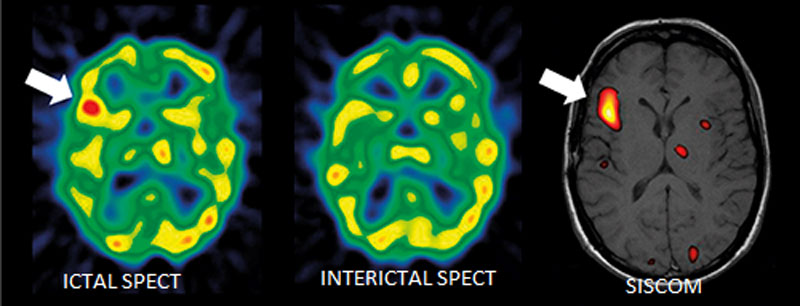

- Современная нейровизуализация (МРТ, ОФЭКТ, SISCOM)

Внедрен современный протокол диагностики эпилептогенных очагов головного мозга — протокол SISCOM (Subtraction Ictal SPECT Co-Registered to MRI)